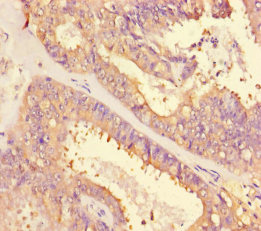

• Immunohistochemistry of paraffin-embedded human endometrial cancer using CSB-PA01629A0Rb at dilution of 1:100